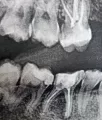

Был сделан контрольный снимок до лечения и после лечения. На снимке, сделанном после лечения, я увидела, что много пломбировочного материала вышло за пределы верхушки корневого канала.

На снимке видно, что один из каналов заполнен не до конца. Я задала вопросы врачу и получила ответ, что все в порядке, работа выполнена правильно и ничего страшного в том, что пломбировочный материал вышел за пределы канала.